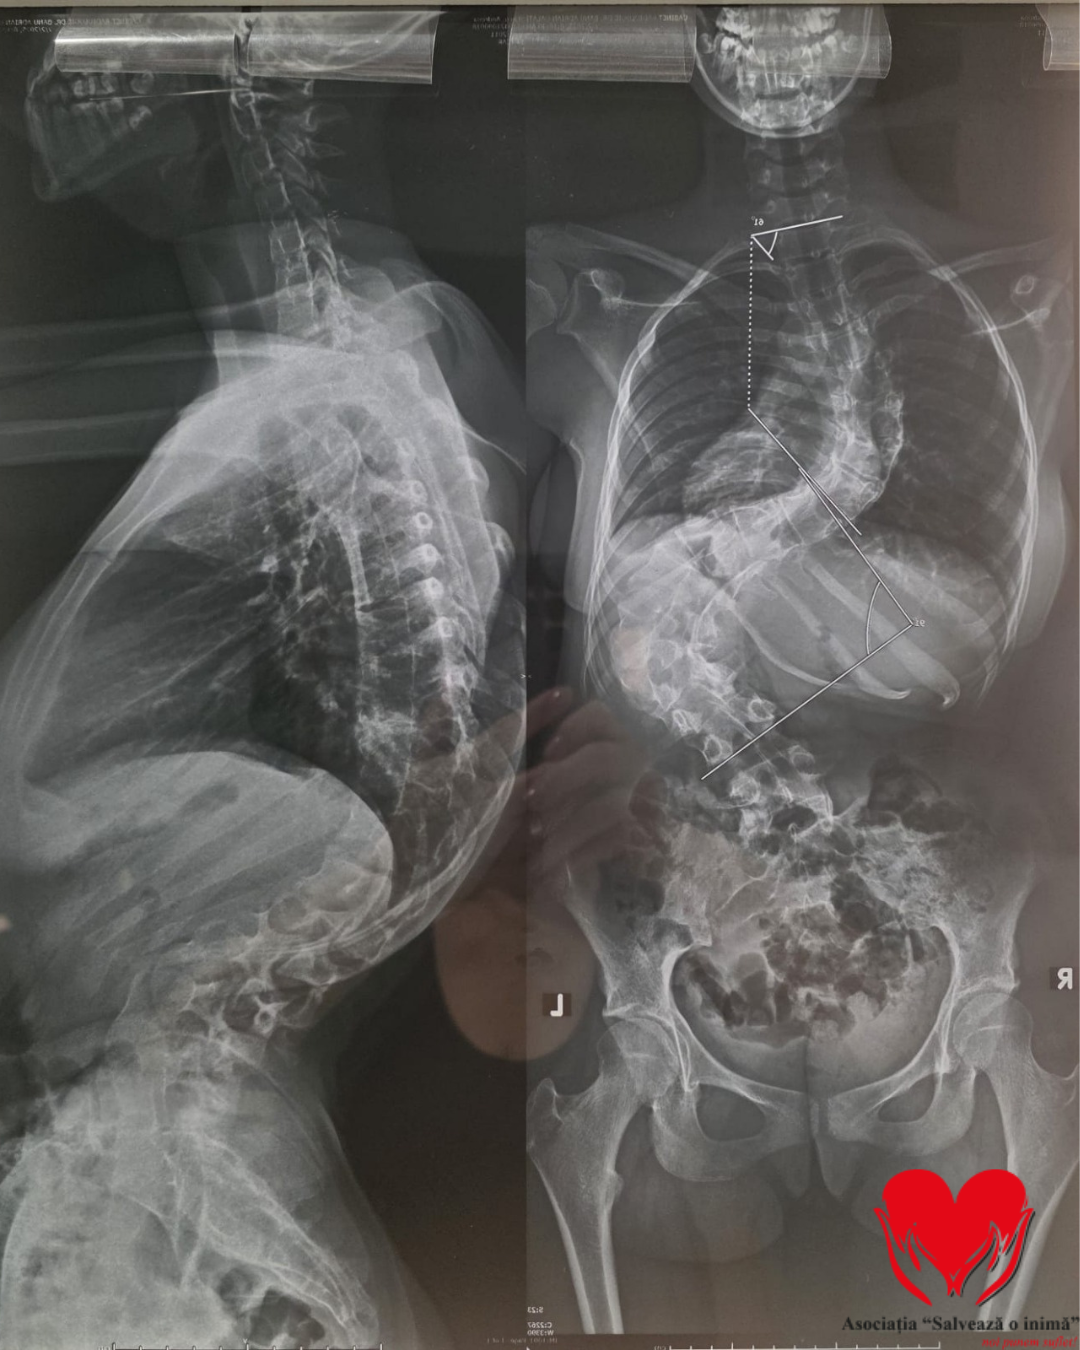

Andreea a fost diagnosticată încă de la o vârstă fragedă cu scolioză. În ciuda tuturor tratamentelor urmate ani la rând – kinetoterapie, fizioterapie, masaj, purtarea corsetului ortopedic și restricții severe – boala a continuat să avanseze. Astăzi, medicii vorbesc despre scolioză severă, cu o curbură de 31 de grade lombar și 61 de grade toracic, valori extrem de periculoase pentru un copil aflat în plină creștere.